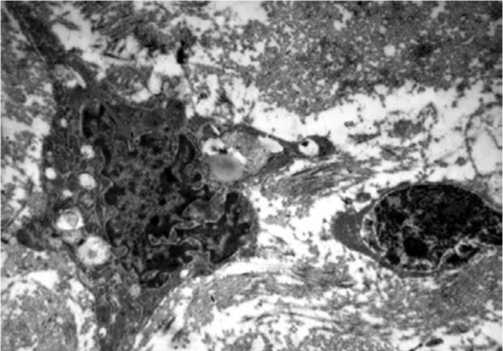

При исследовании электронных микроскопических снимков на увеличении 2500 выявлено, что остеокласты характеризуются большим количеством включений в цитоплазме, что характеризует активную резорбцию костной ткани. Отмечается наличие значительного количества остеобластов с цитоплазмой, богатой органеллами. Это свидетельствует о наличии активных процессов остеосинтеза, что является типичным для репарации костной ткани (Рис. 4).

Рис. 4. Туннелизация с криовоздействием 3 сек. Остеокласт (стрелка) с включениями в цитоплазме. Остеобласт. Электронная микрофотография. Увеличение х2500.